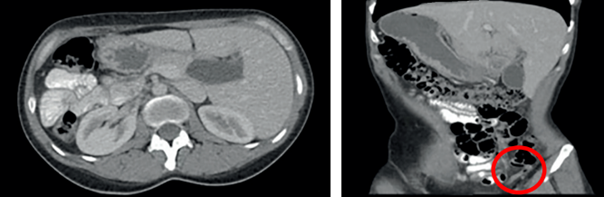

Paciente femenina de 34 años, quien consultó a urgencias por cuadro clínico de tres días de evolución consistente en dolor abdominal generalizado, tipo cólico, constante, de intensidad progresiva, que se irradiaba a región lumbar y posteriormente migró a fosa iliaca izquierda, asociado a distensión abdominal, náuseas e hiporexia. Como antecedente de importancia, fue diagnosticada con situs inversus totalis a los 24 años por ecografía para estudio de lumbalgia crónica. Al examen físico presentaba signos vitales dentro de límites normales y dolor a la palpación abdominal generalizada, de mayor intensidad en fosa iliaca izquierda, sin signos de irritación peritoneal. El hemograma no mostró leucocitosis ni neutrofilia, por lo que se solicitó ecografía abdominal, la cual reportó edema de la pared del apéndice cecal con presencia de un fecalito en su interior. Durante la evolución clínica la paciente presentó mejoría significativa del dolor; debido a la pobre correlación clínico-radiológica, se decidió confirmar el diagnóstico con una tomografía computarizada con contraste (Figura 2), que mostró la presencia de apendicitis con localización en fosa iliaca izquierda. En consecuencia, se inició antibioticoterapia y se procedió a realizar apendicectomía vía laparoscópica, con la cual se identificó la transposición de órganos abdominales y un apéndice en fase edematosa en la fosa iliaca izquierda (Figura 3), junto con múltiples adherencias de epiplón a la pared abdominal en hemiabdomen inferior y focos de endometriosis en fimbria y región ampular de la trompa izquierda con congestión, clasificados como grado III. Se llevó a cabo la liberación del apéndice y se completó la apendicectomía sin complicaciones. El diagnóstico de apendicitis se confirmó mediante el estudio histopatológico.